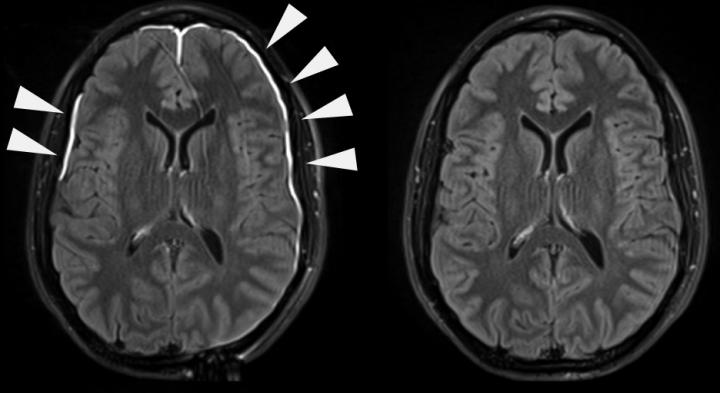

The study came about from an observation on MRI scans of adult patients who experienced a concussion or mTBI. Around half of patients with mTBI show evidence of injury to blood vessels in the meninges, which appears on MRI scans as a vascular dye leaking out of the damaged vessels.

Dr. McGavern's team found that while most patients had repaired their leaky blood vessels within 20 days, 17 percent of patients still showed leakage on their MRI scans three months after injury, indicating ongoing meningeal damage and incomplete recovery.